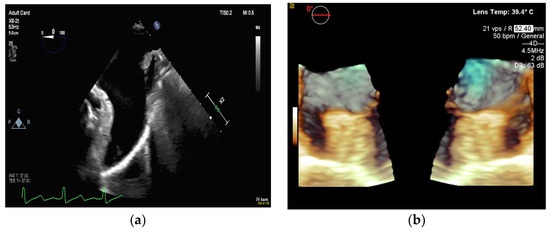

4.2.1. Transseptal Puncture

4.2.2. Left Atrial Appendage Occlusion

4.2.3. Mitral Valve Repair

4.2.4. Atrial Septal Defect Occlusion

4.2.5. Paravalvular Leak Closure

4.2.6. Transcatheter Aortic Valve Replacement